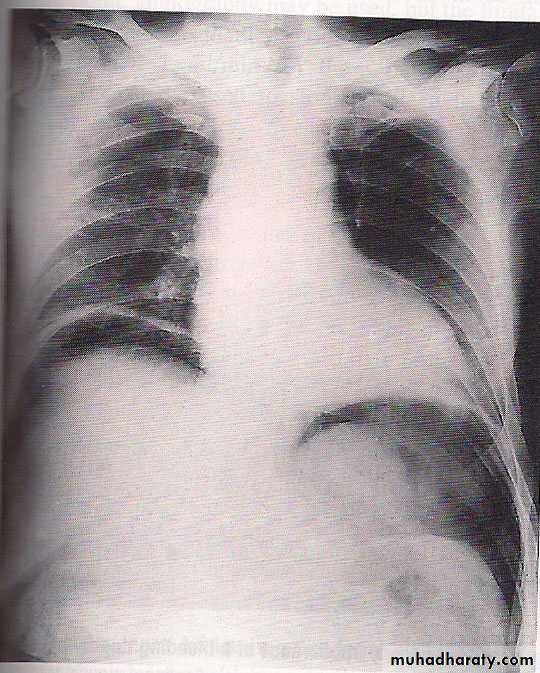

An erect plain chest radiograph will reveal free gas under the diaphragm in 85 per cent of cases with perforated peptic ulcer, but CT imaging is more accurate. All patients should have serum amylase performed, as distinguishing between peptic ulcer perforation and pancreatitis can be difficult.Treatment